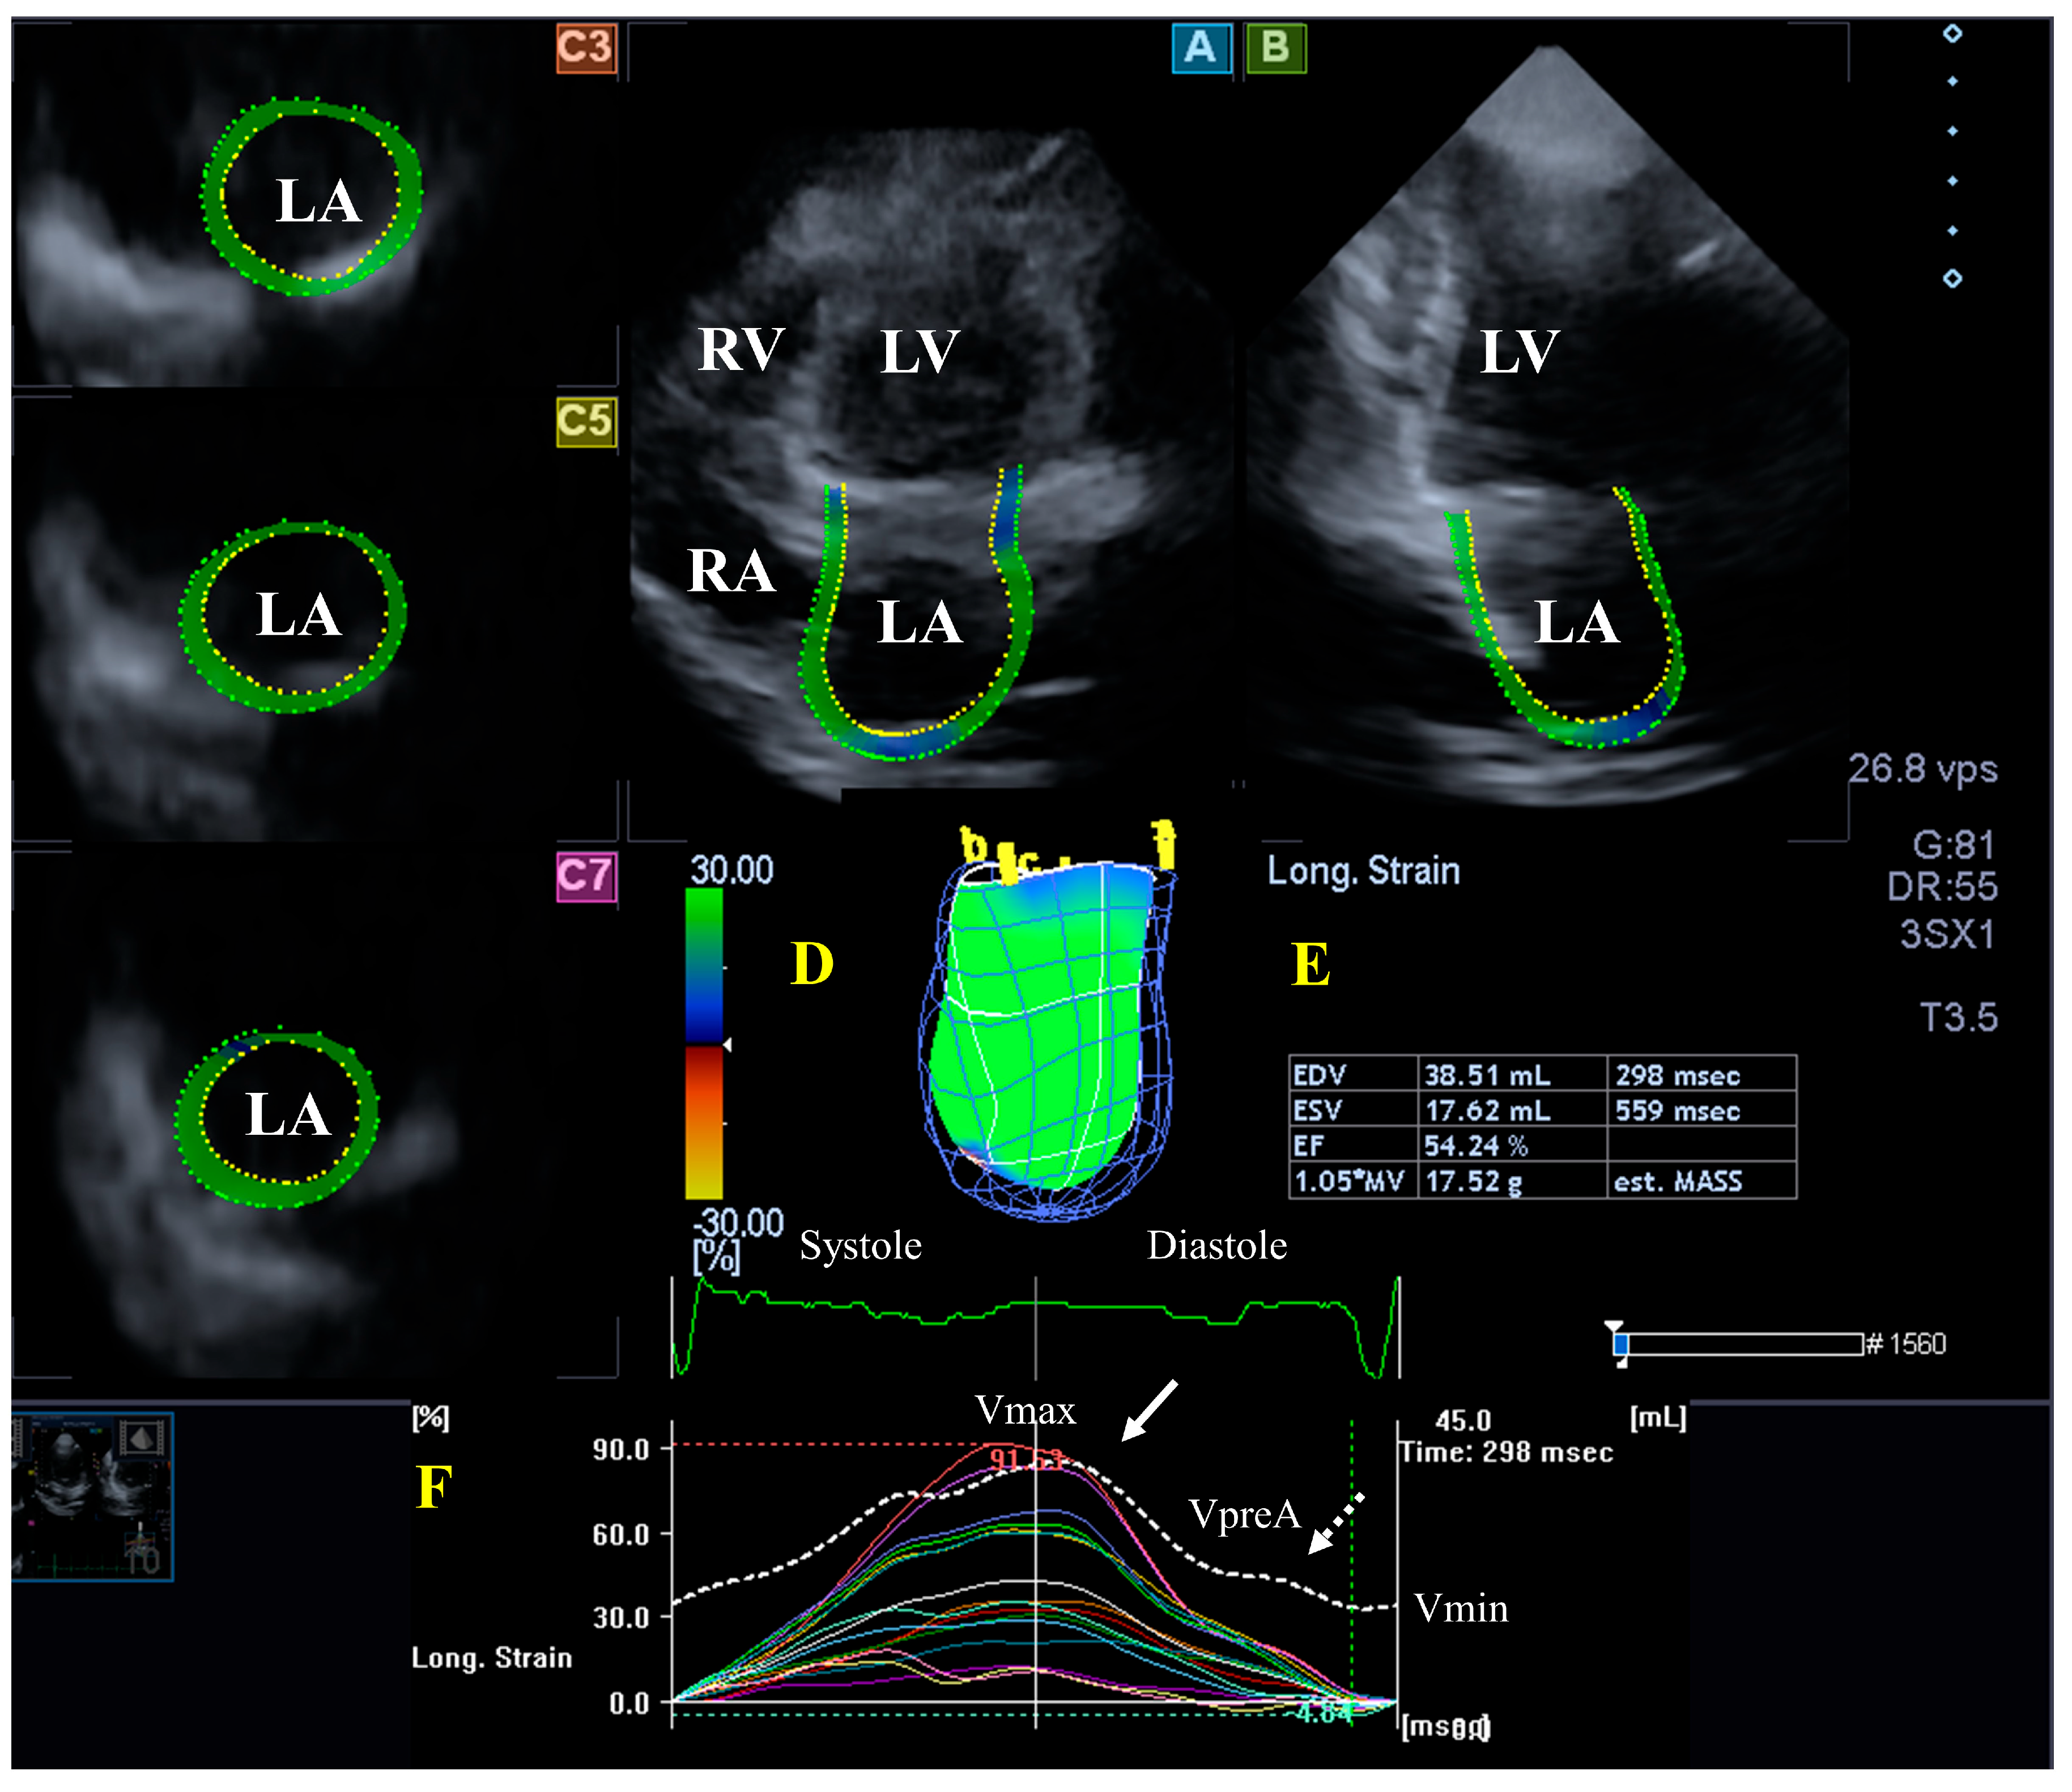

3.2. Left Atrium

- Nemes, A.; Marton, I.; Domsik, P.; Kalapos, A.; Pósfai, É.; Modok, S.; Borbényi, Z.; Forster, T. Characterization of left atrial dysfunction in hypereosinophilic syndrome—Insights from the Motion analysis of the heart and great vessels by three-dimensional speckle tracking echocardiography in pathological cases (MAGYAR-Path) Study. Rev. Port. Cardiol. 2016, 35, 277–283. [Google Scholar] [CrossRef]